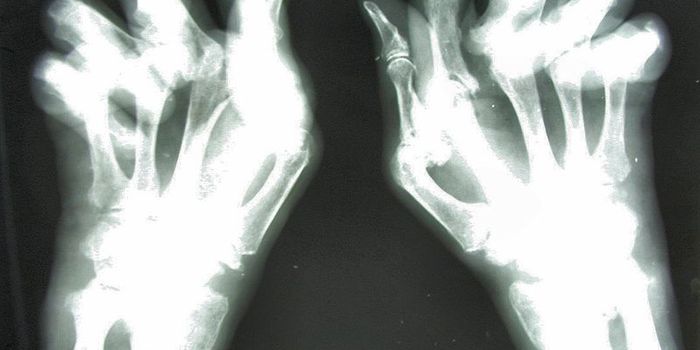

JUN 19, 2018Clinical & Molecular DXThere is a new way to diagnose arthritis and watch its progression slowly over time to determine the best route of treat ...